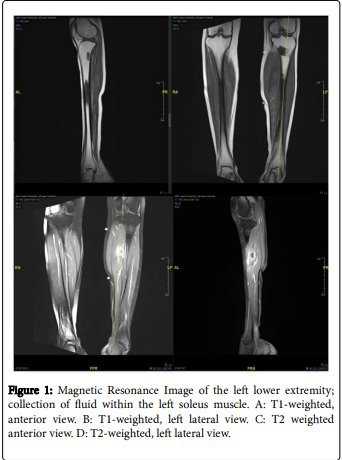

#Influenza and Coxsackie are the most common causes of viral #pyomyositis. Influenza B especially involves the calf.